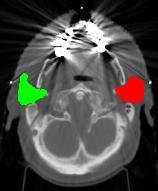

This paper presents the segmentation of bilateral parotid glands in the Head and Neck (H&N) CT images using an active contour based atlas registration. We compare segmentation results from three atlas selection strategies: (i) selection of “single-most-similar” atlas for each image to be segmented, (ii) fusion of segmentation results from multiple atlases using STAPLE, and (iii) fusion of segmentation results using majority voting. Among these three approaches, fusion using majority voting provided the best results. Finally, we present a detailed evaluation on a dataset of eight images (provided as a part of H&N auto segmentation challenge conducted in conjunction with MICCAI-2010 conference) using majority voting strategy.